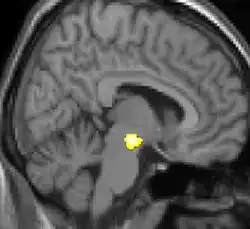

Positron emission tomography (PET) scans indicate the brain areas which are activated during attack only, compared to pain free periods. These pictures show brain areas that are active during pain in yellow/orange color (called "pain matrix"). The area in the center (in all three views) is activated only during cluster headaches. The bottom row voxel-based morphometry shows structural brain differences between individuals with and without CH; only a portion of the hypothalamus is different.[36]